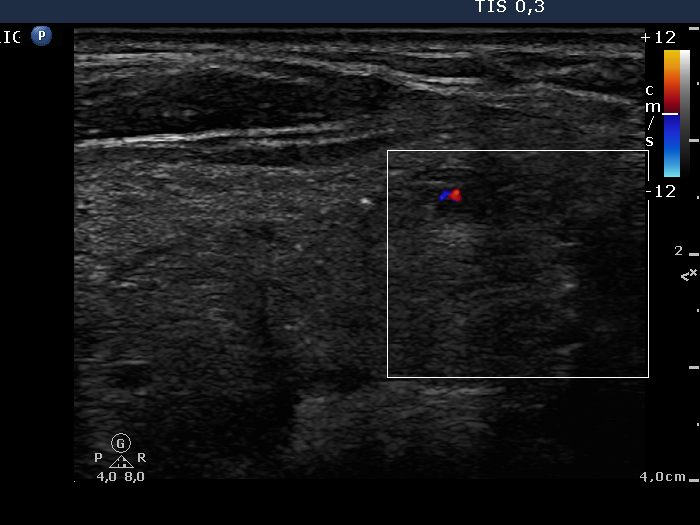

Benign nodular hyperplasia - Case 1. (ultrasonographic picture 5)

Right lobe and isthmus, longitudinal view, color Doppler method. The vascularization is not specific.